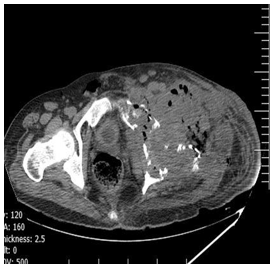

Abdominal ultrasound did not show hepatic or other visceral involvement. Pelvic ultrasound indicated a collection include necrotic tissues, gas bubbles, and discharge in the left side of pelvic cavity. Chest x-ray (CXR) was normal. A computed tomography scan showed destruction lesions in the left hemi pelvis, sacrum, and the left proximal femur, as well (Figures 2-5).

.Figure 2: CT-scan of pelvic show distraction of iliac bone with a mass with air in the mass